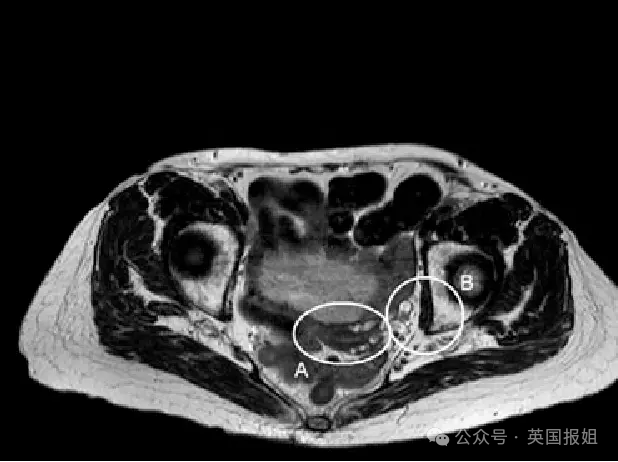

来自土耳其伊斯坦布尔巴赫切谢希尔大学的医生们提交了一位新病例:

一名35岁的女性身体频频失控,生殖器一直刺痛,时常莫名其妙就濒临性高潮,甚至上着上着班就直接不行了……

最终,医生们推测,她可能患上了两种存在临床关联的障碍……

生殖器不安综合征(RSG)和持续性生殖器唤起障碍(PGAD)。